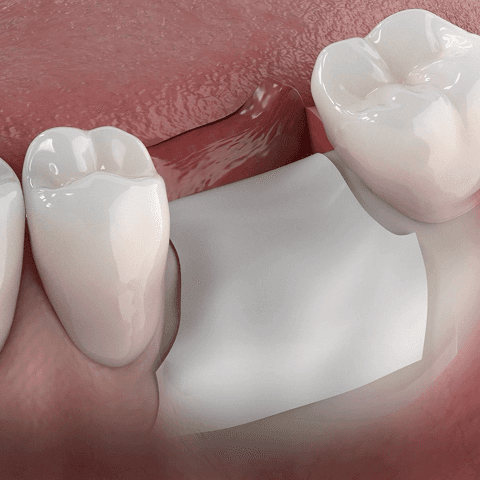

02

차폐막을 덮어 뼈재생 환경을 조성

이식한 뼈 위에 차폐막을 씌워 안정적인 치유 환경을 만들어주고, 뼈가 제대로 형성되도록 돕습니다.

03

수개월 간 치유기간 확보

일반적으로 3~6개월의 회복기간 동안 뼈가 안정적으로 자라도록 기다립니다.